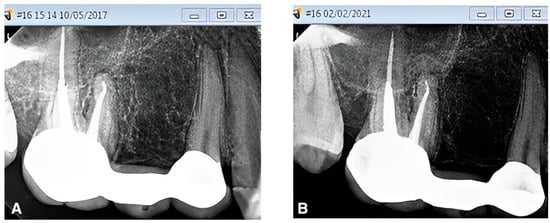

A healthy periapex PAI 1 was described as a healthy periapex, which had the normal width of permanent ligament space and surrounding bone that looked normal. The evaluation of all other PAI scores (2,3,4,5) was mentioned as apical periodontitis. The chi-square test was employed for statistical analysis, with a significance level of p < 0.05. Out of 70 recalled patients, the male students had performed a total of 20 post and core treatments, whereas the female undergraduate students had completed post and core treatments for 50 cases. A total of 90% (n = 18) of the teeth in group I with no gap between the residual gutta-percha and the post were found to be healthy, while 10% (n = 2) were found to be diseased (Figure 1). In group II, there were 66.7% (n = 22) of normal teeth and 33.3% (n = 11) of diseased teeth, with a gap of more than 0 mm to less than 1 mm between the post end and the remaining gutta-percha (Figure 2). However, 58.8% (n = 10) of group III patients with a gap of more than 1 mm between the post end and the remaining gutta-percha were found to be healthy, whereas 41.2% (n = 7) were found to be diseased. (Figure 3). A total of 32% (n = 16) endodontically treated teeth were found diseased and treated by the female students while 68% (n = 34) of teeth were found normal. A total of 20% (n = 4) endodontically treated teeth were found diseased and treated by the male students while 80% (n = 16) of teeth were found normal. (Figure 4 and Figure 5) The quadrant wise treated teeth included for follow up examinations were 36 maxillary anteriors, 8 maxillary posteriors, 12 mandibular anteriors, and 14 mandibular posteriors. Among the maxillary anteriors, 69.4% (n = 25) of teeth were found normal however 30.6% (n = 11) of teeth were found diseased. Among the maxillary posteriors, 50% (n = 4) of teeth were found normal however 50% (n = 4) of teeth were found diseased. Among the mandibular anteriors, 83.3% (n = 10) of teeth were found normal however 16.7% (n = 2) of teeth were found diseased. Among the mandibular posteriors, 78.6% (n = 11) of teeth were found normal however 21.4% (n = 3) of teeth were found diseased. (Figure 4 and Figure 5).

Figure 4. Association of disease status with respect to gender, quadrant, and gap categories. NS = non-significant.

Figure 5. Graphic illustration of association of disease status with respect to gender, quadrant, and gap categories.